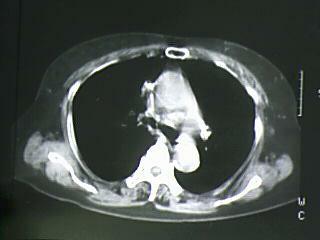

以下是引用bmw011在2009-4-14 19:14:00的发言:[br]右肺继发型肺结核---纵隔淋巴结多发钙化----左肺支扩。支持

以下是引用杀毒软件在2009-4-14 17:52:00的发言:[br]考虑---右肺继发型肺结核---纵隔淋巴结多发钙化----左肺支扩

以下是引用黑白光影在2009-4-14 20:36:00的发言:[br]右肺继发型肺结核;左下慢性支气管炎性病变。